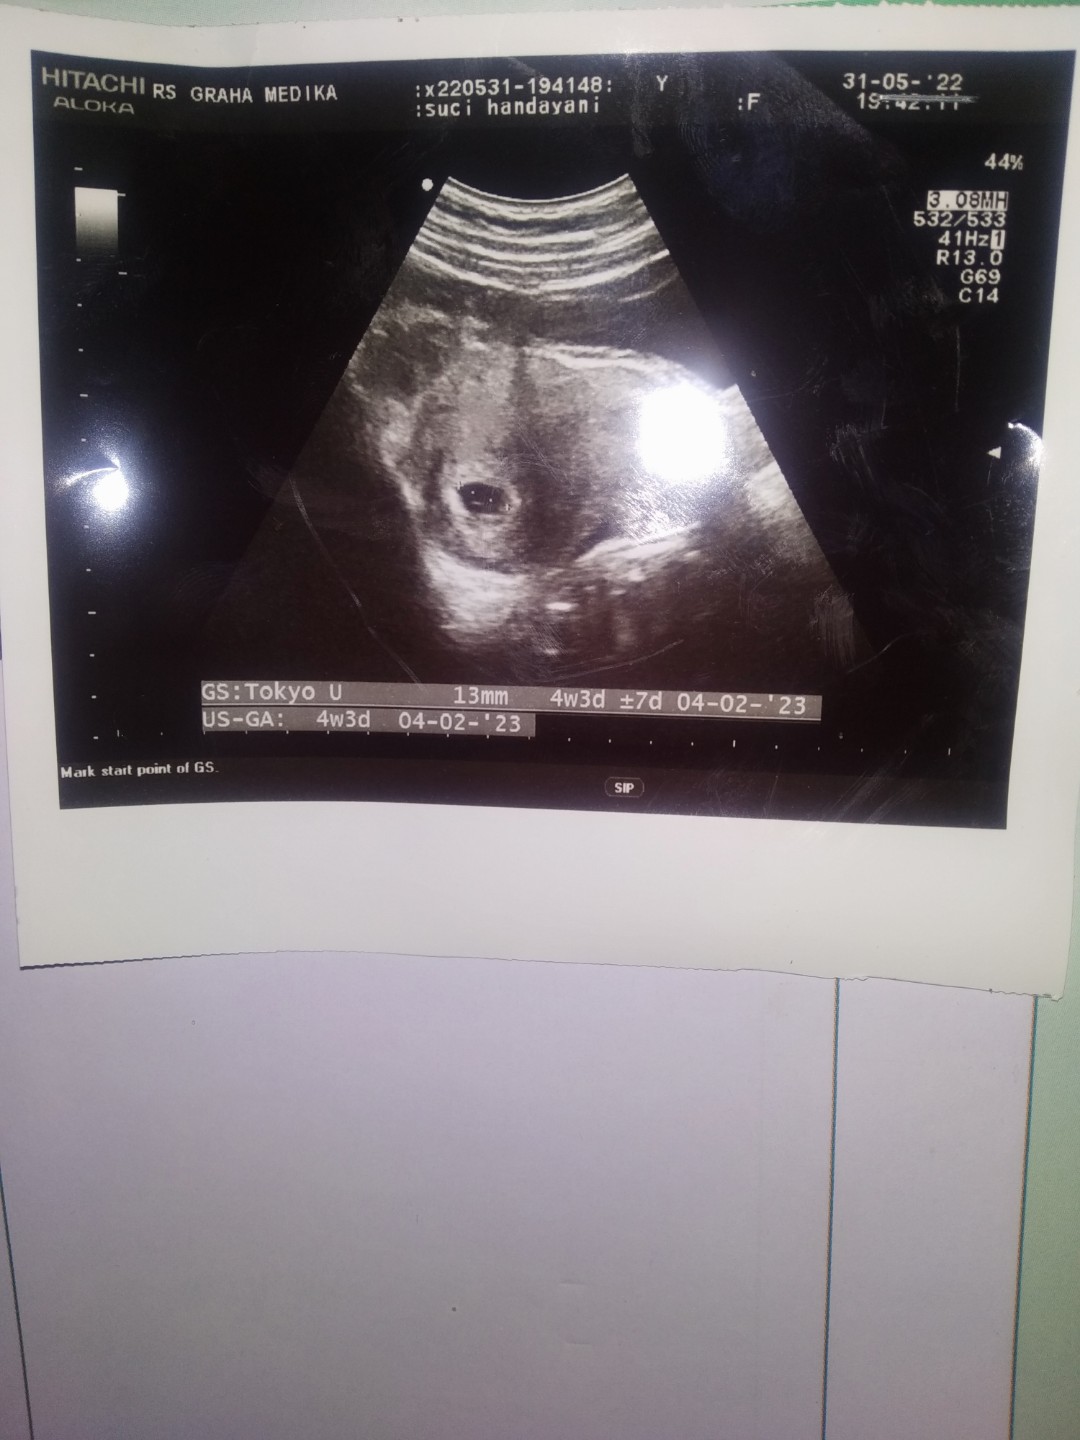

udah Bun, Kemarin dari Dokter udah USG juga, ini hasil usgnya bun

udah d Periksa Bun, Di uSg juga .. ktanya baik, dikasih obat penguat

iyaa Bun baik, Udah Periks Kemarin juga Udh Usg